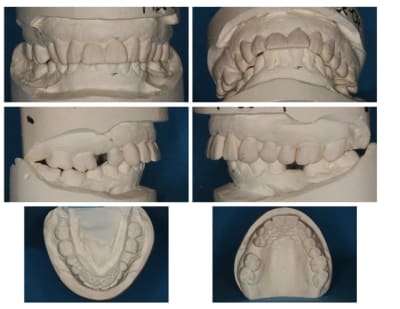

Suite :

Paro stable, furcation normale.

Patiente ne désire pas de chirurgie style Lefort (pour le gummy smile), ni d'ortho.

J'ai placé 2 implants (14 et 35)

Le bridge 34-X-36 était brisé et troué (pour une endo), et la patiente désirait des dents unitaire.

J'ai placé des provisoires de 13 à 23 suite à

l'élongation de 13 à 23 et apectomie 12.